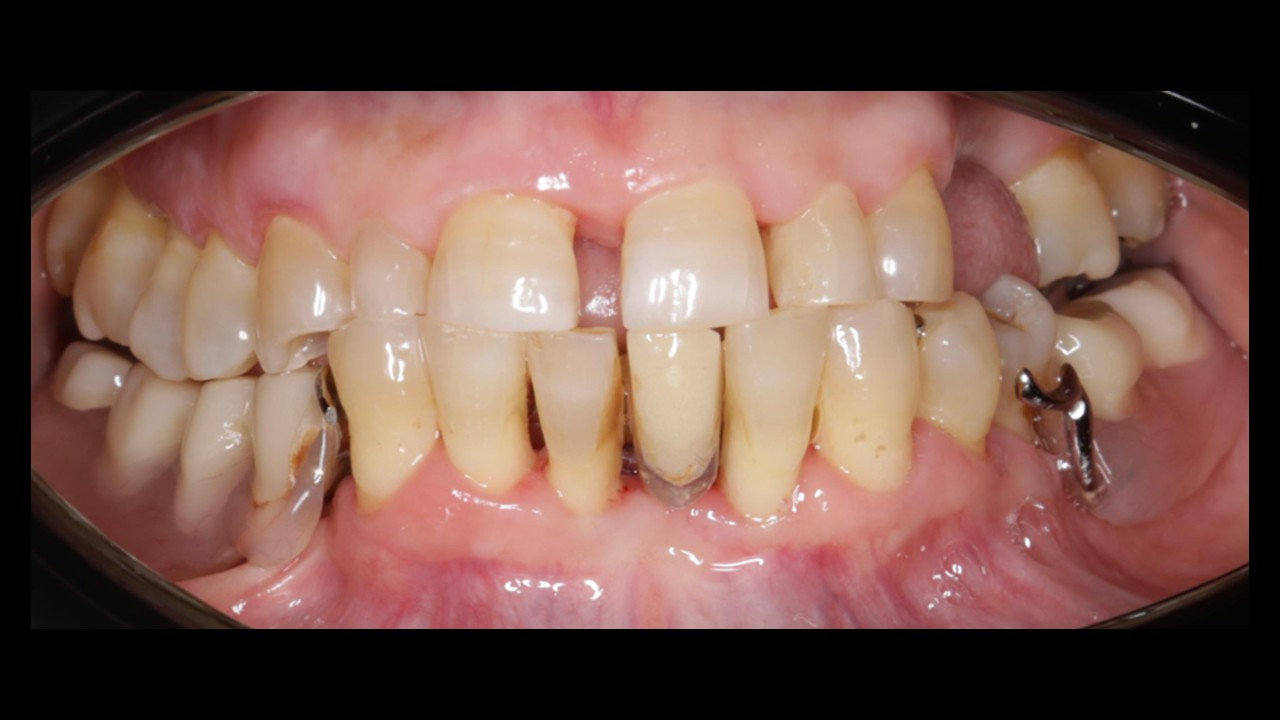

Exodoncia dientes inferiores + IOI (5)

12 de diciembre de 2025 · Dr. Miroslav Andreucic

Caso Clínico Dr. Miroslav AndreucicOdontólogo especializado en periodoncia e implantología, con más de 10 años de experiencia en salud pública y privada.Datos personales paciente:Nombre: I.J.S.Edad: 56 añosGénero: FEMA…